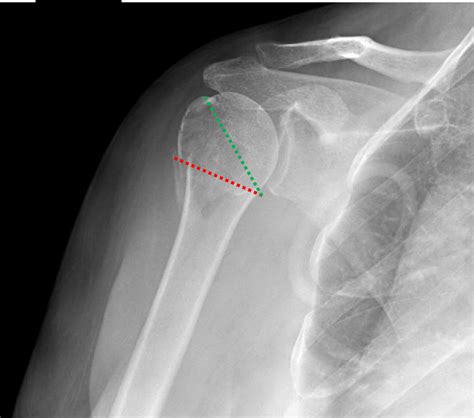

• Imaging Tests: X-rays are the primary imaging tool used to diagnose proximal humerus fractures. In some cases, additional tests such as CT scans or MRIs may be ordered to provide more detailed images.

Classification of Proximal Humerus Fractures

Proximal humerus fractures are classified based on the location and pattern of the fracture. The most common classification systems include:

• Neer Classification: This system categorizes fractures based on the number of parts involved (one, two, three, or four parts).

• AO/OTA Classification: This system uses a more detailed coding system to describe the fracture pattern and severity.

Understanding the classification of the fracture helps healthcare providers determine the appropriate treatment plan.